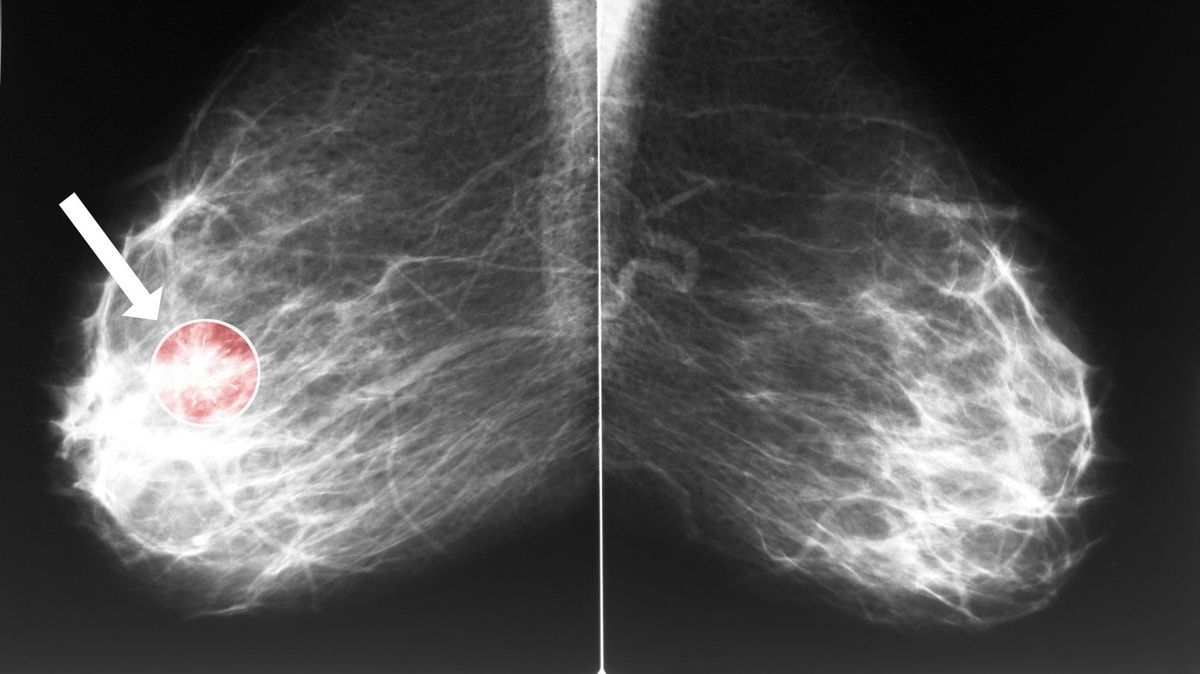

Ученые из Манчестерского университета оценили выживаемость и частоту развития рака молочной железы у носителей мутаций BRCA1 и BRCA2 без

Ученые из Манчестерского университета оценили выживаемость и частоту развития рака молочной железы у носителей мутаций BRCA1 и BRCA2 без онкологического анамнеза, выбравших профилактическую мастэктомию или наблюдение. Результаты исследования опубликованы в Journal of Clinical Oncology.